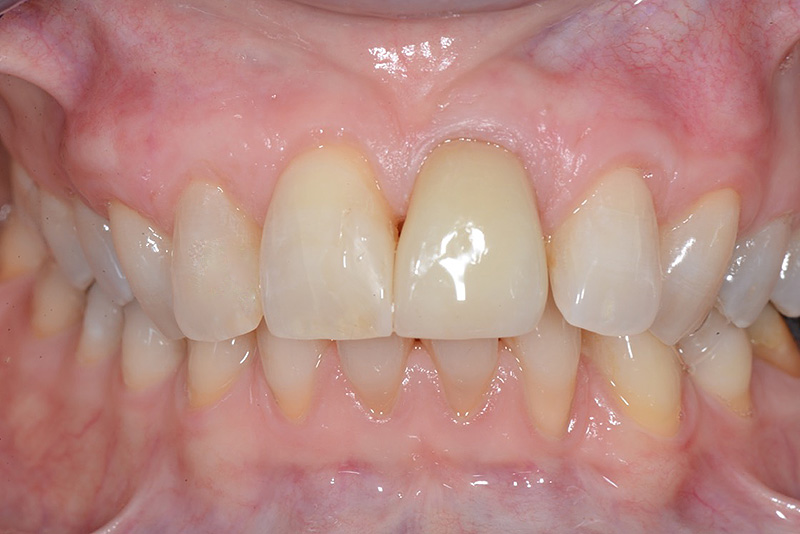

PREMESSA: in seguito all’estrazione dell’incisivo laterale superiore di destra, resasi necessaria per cause batteriche, si decide di affrontare il caso con il posizionamento di un impianto in sostituzione dell’elemento mancante dopo guarigione del sito infetto. Con tecniche rigenerative sia dei tessuti ossei mancanti a causa dell’infezione pregressa, sia dei tessuti gengivali che appaiono inizialmente troppo spostati in alto, si ripristina una corretta morfologia delle parabole (contorni) gengivali e delle papille interdentali (triangoli di gengiva tra due denti vicini).

Vengono utilizzati 2 tipi di provvisori: il primo, cementato ai denti vicini, viene utilizzato dal momento dell’estrazione del dente fino ad impianto osteointegrato (circa 6 mesi); il secondo, avvitato direttamente all’impianto, ha una funzione di prova estetica ma soprattutto di guida per la maturazione dei tessuti gengivali peri-implantari portandoli verso la maturazione completa prima di posizionare la corona finale in disilicato di litio.